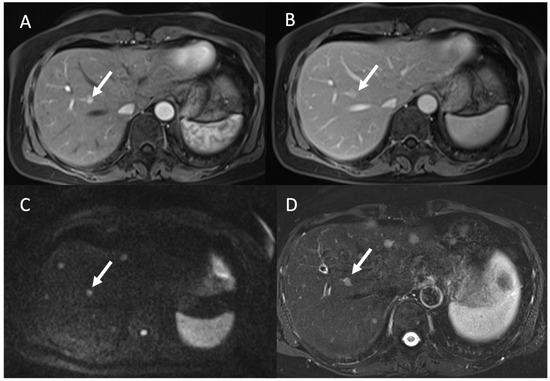

3.2. Liver Metastases

- G. d’Assignies; Fina, P.; Bruno, O.; Vullierme, M.; Tubach, F.; Paradis, V.; Sauvanet, A.; Ruszniewski, P.; Vilgrain, V. High sensitivity of diffusion-weighted MR imaging for the detection of liver metastases from neuroendocrine tumors: Comparison with T2-weighted and dynamic gadolinium-enhanced MR imaging. Radiology 2013, 268, 390–399. [Google Scholar] [CrossRef]

- Ronot, M.; Clift, A.; Baum, R.; Singh, A.; Kulkarni, H.; Frilling, A.; Vilgrain, V. Morphological and Functional Imaging for Detecting and Assessing the Resectability of Neuroendocrine Liver Metastases. Neuroendocrinology 2018, 106, 74–88. [Google Scholar] [CrossRef]